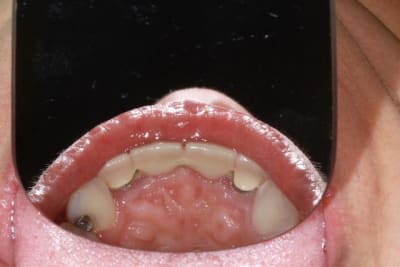

Patiente sympa, 30 ans, un bridge ceramo-métal fait il y a 10 ans, en fin de vie.

Les endo et les IC dans les 12-22 sont sublimes...et ça a durer 10 ans....incroyable...Il y a pas de la paro aussi ?